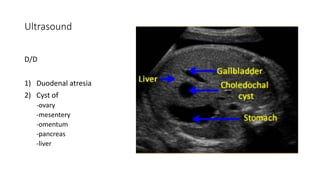

Prenatal diagnosis

Ultrasound

Earliest diagnosis at 25 weeks

Ultrasound

D/D

1) Duodenal atresia

2) Cyst of

-ovary

-mesentery

-omentum

-pancreas

-liver

Ultrasound D/D 1) Duodenal atresia 2)Cyst of -ovary -mesentery -omentum -pancreas -liver